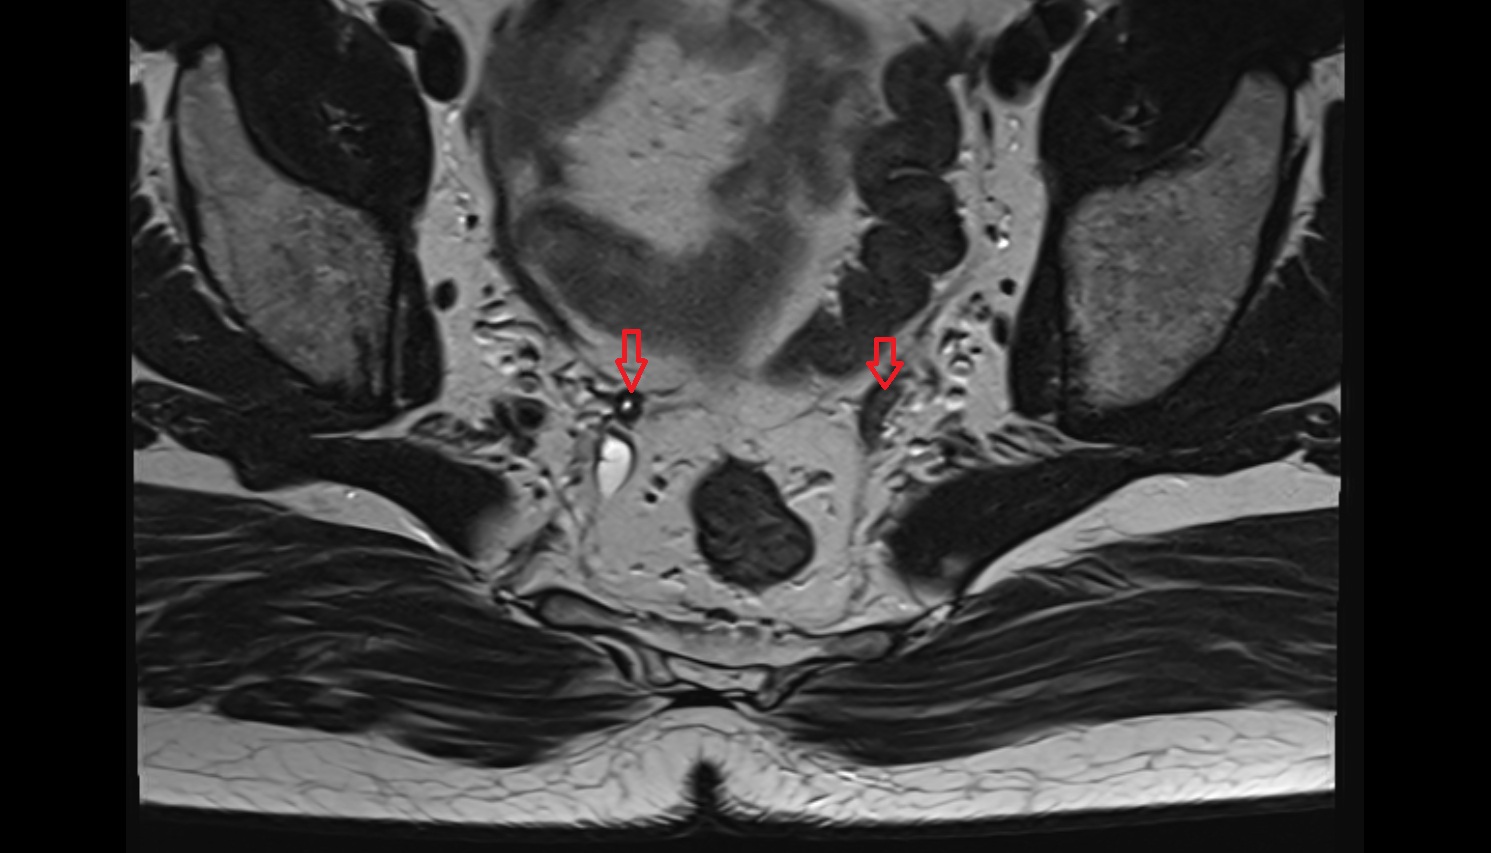

- Inguinal lymph nodes

- Intermediate lacunar external iliac lymph nodes

- External iliac lymph nodes

- Obturator lymph nodes